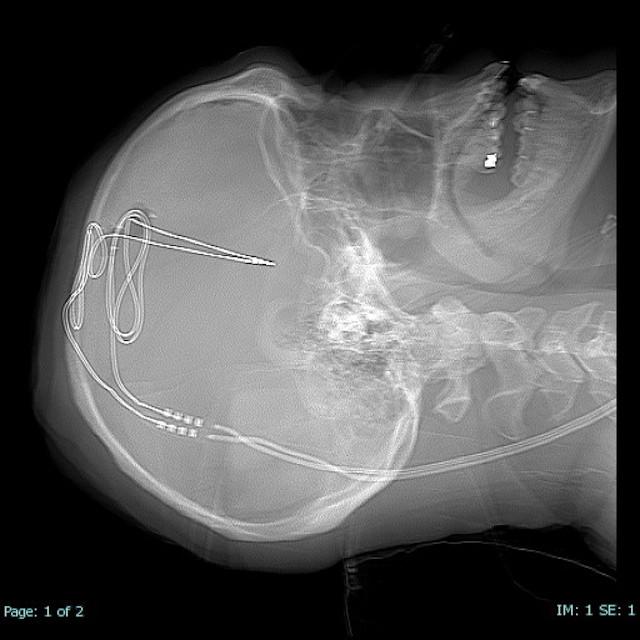

The team successfully implanted a Medtronic DBS device in the addiction and reward center of the brain. The trial's first participant is a 33-year-old man, who has struggled with substance use disorder, specifically excessive opioid and benzodiazepine use, for more than a decade with multiple overdoses and relapses.

DBS, or brain pacemaker surgery, involves implantation of tiny electrodes into specific brain areas to regulate the structures involved in addiction and behavioral self-control. This study will also investigate the mechanism of the addiction in the brain. The U.S. Food and Drug Administration has approved DBS for treating patients with Parkinson's disease, essential tremor, dystonia, epilepsy, and obsessive-compulsive disorder. The RNI team routinely uses DBS to treat patients with these disorders.